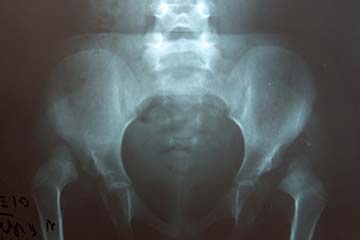

Αναπτυξιακή δυσπλασία του ισχίου

Αναπτυξιακή δυσπλασία του ισχίου (DDH – Developmental Dysplasia of the Hip), είναι ο όρος που καλύπτει το σύνολο των παθολογικών καταστάσεων του νεογνικού και βρεφικού ισχίου.

Διακρίνεται στο αληθές εξάρθρημα του ισχίου με την κεφαλή εκτός της κοτύλης, το ασταθές ισχίο που η κεφαλή ανατάσσεται ή εξαρθρώνεται με τις κινήσεις και στην ανεπάρκεια (λοξότητα) της κοτύλης που οδηγεί σε μερική κάλυψη της μηριαίας κεφαλής.

Ο υπερηχογραφικός έλεγχος καταγράφει τον βαθμό δυσπλασίας του ισχίου (ταξινόμηση Graf). Αναλόγως του κάθε περιστατικού ακολουθεί  ακτινολογική εξέταση και ίσως μαγνητική και αξονική τομογραφία ή αρθρογράφημα.